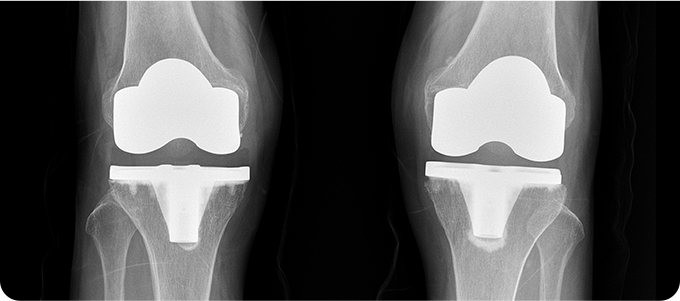

전치환술

전치환술 관련 이미지

• 관절염 3기 말, 4기인 경우

• 전·후방 십자인대가 손상된 경우

• 오다리, X다리가 심한 경우

• 비수술적 치료로 증상 호전이 되지 않을 경우

무릎 관절염

인공관절치환술

퇴행성 관절염으로 닳아버린 연골과 변형된

뼈 표면만을 정밀하게 절제합니다.

무릎의 굽힘·펴짐과 안정성을 고려해

인공관절을 삽입, 무릎 중심축을 바로 잡아줍니다.